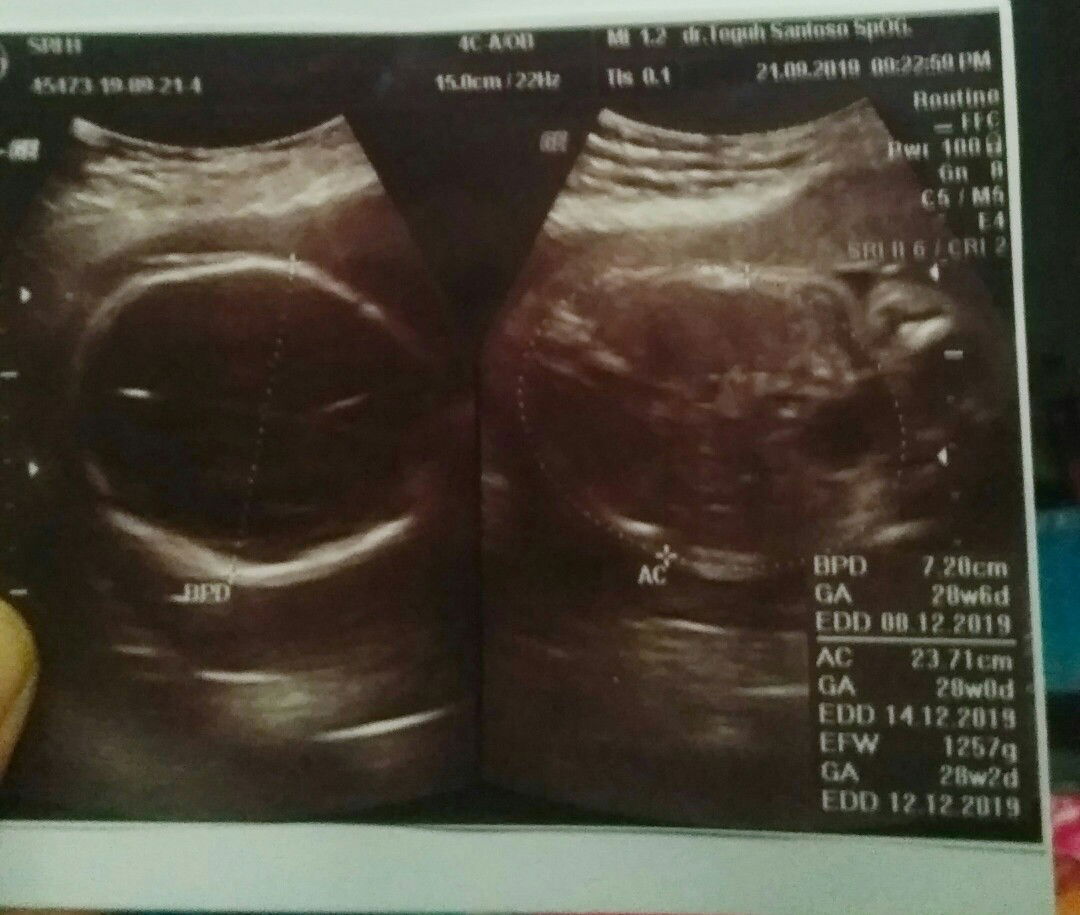

Hai bund,ini hasil USG aq,tp aq tdk bs mgerti dgn hasilnya trtama Hpl yg benar itu yg mn,,mohon bantuannya?